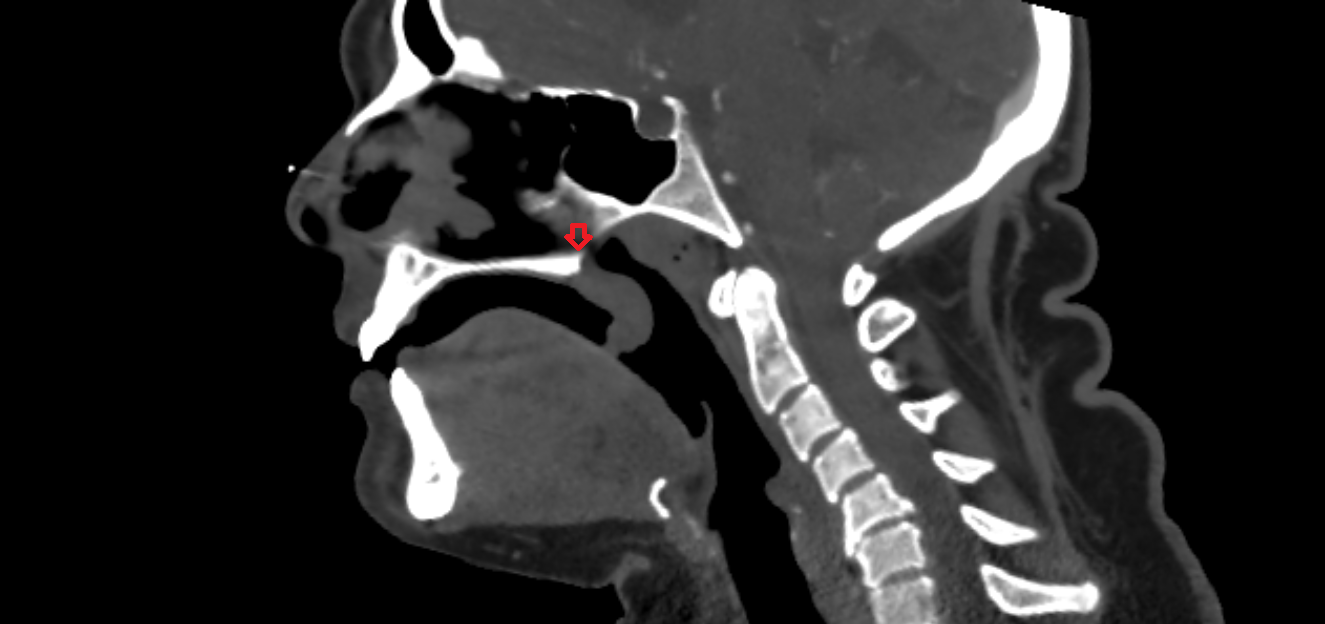

- Temporomandibular joint

- Mandibular condyle

- Mandibular fossa

- Articular eminence

- Articular surface of mandibular fossa

- Articular tubercle